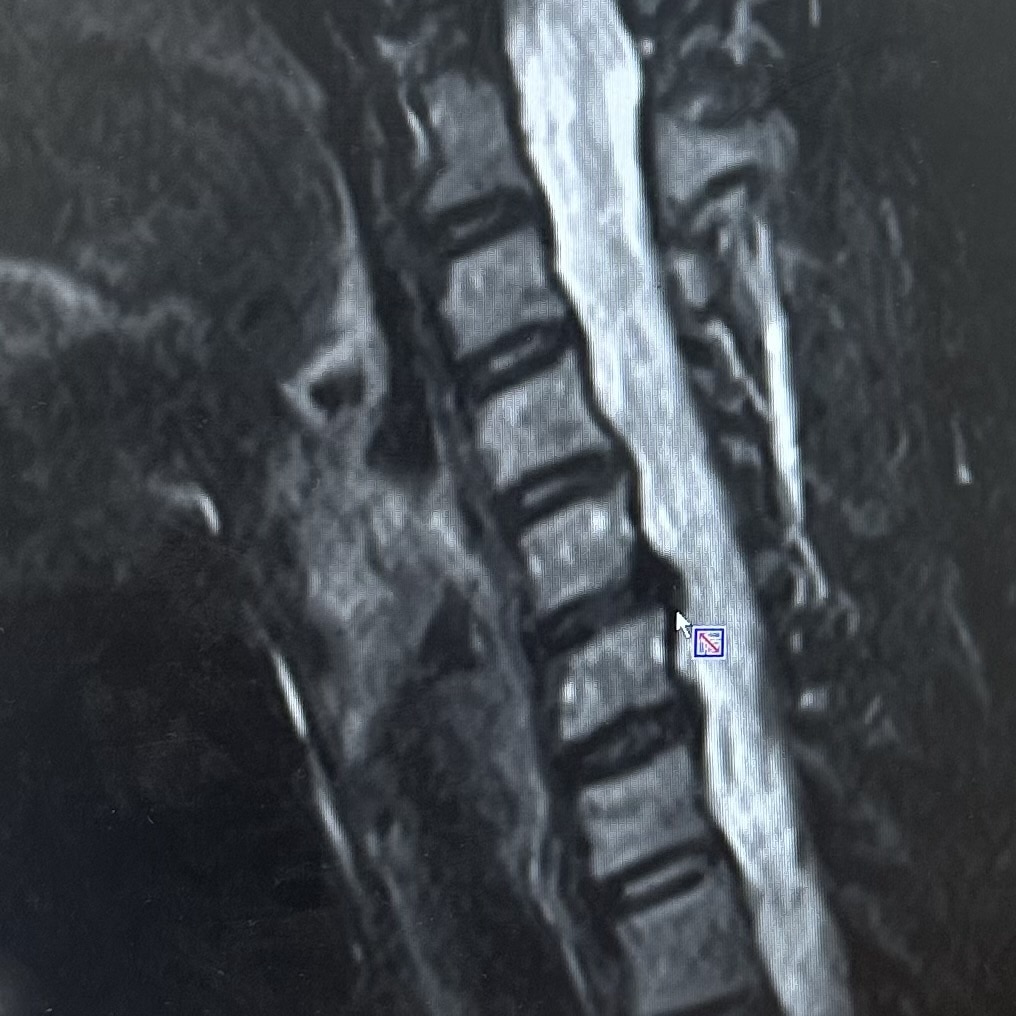

私の頚椎ヘルニア。。。

左から見た横顔、というか横首😂の輪切りです。

四角いのが頚椎の骨

白いのが脊髄液

四角いのの継ぎ目の黒いところが椎間板。

矢印のところ、

黒いものが右にぴよっと出ているのが

私の椎間板ヘルニアです😭

おまえか!悪さしてるのは!と😠